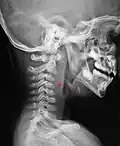

L'espace rétropharyngien est un espace anatomique médian situé entre la paroi postérieure du pharynx et la colonne vertébrale recouverte des muscles prévertébraux et de la lame prévertébrale du fascia cervical.

L'espace rétropharyngien est limité en haut par la partie basilaire de l'os occipital et se prolonge à sa base par le médiastin à partir de la fourchette sternale.

Latéralement, il est limité par la lame sagittale qui le sépare de l'espace latéro-pharyngien et de la gaine carotidienne.

Un raphé médian présent dans cet espace peut y favoriser des infections : les abcès rétropharyngiens[2]. En particulier, des infections dentaires peuvent descendre par cet espace jusqu'au médiastin postérieur, puis sans traitement, affecter les espaces adjacents.